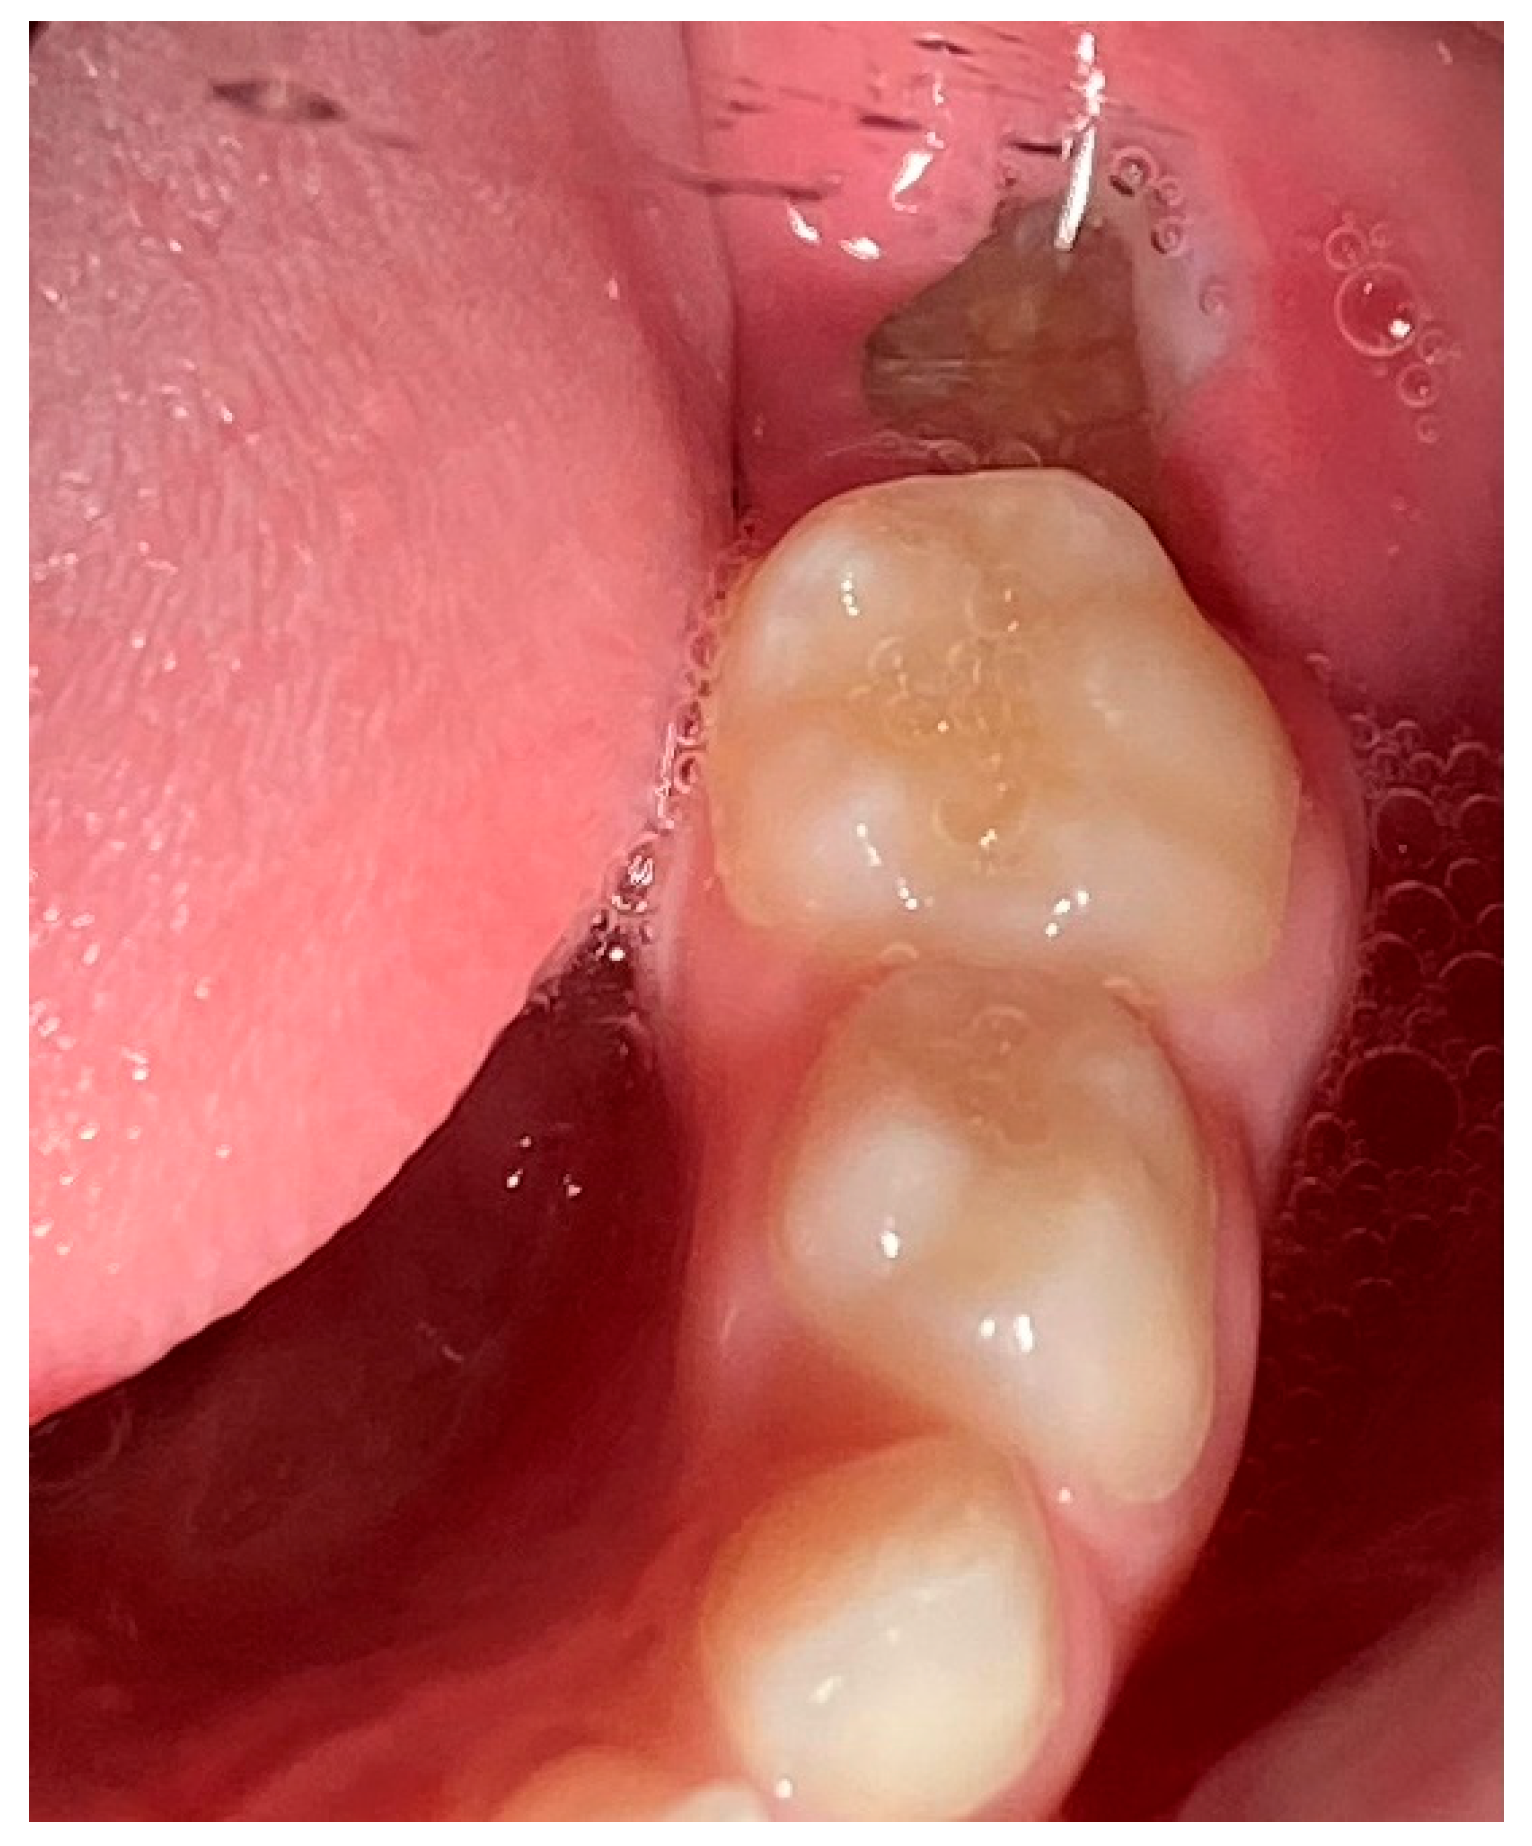

2. Case Presentation